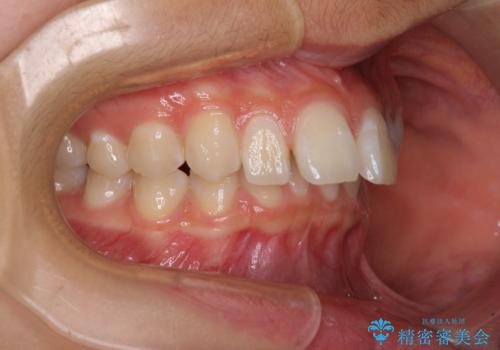

深い咬み合わせで前方に煽られた前歯 高校生のインビザライン矯正治療

- 前歯の隙間と前方に飛び出していることを気にして来院された患者様です。

奥歯の咬み合わせを見ると、上顎が下顎に対して相対的に前方にありました。

咬み合わせも深くなっていたため、上顎臼歯を後方に移動させつつ、下顎の小臼歯を直立させ、奥歯の咬み合わせを改善する必要があります。